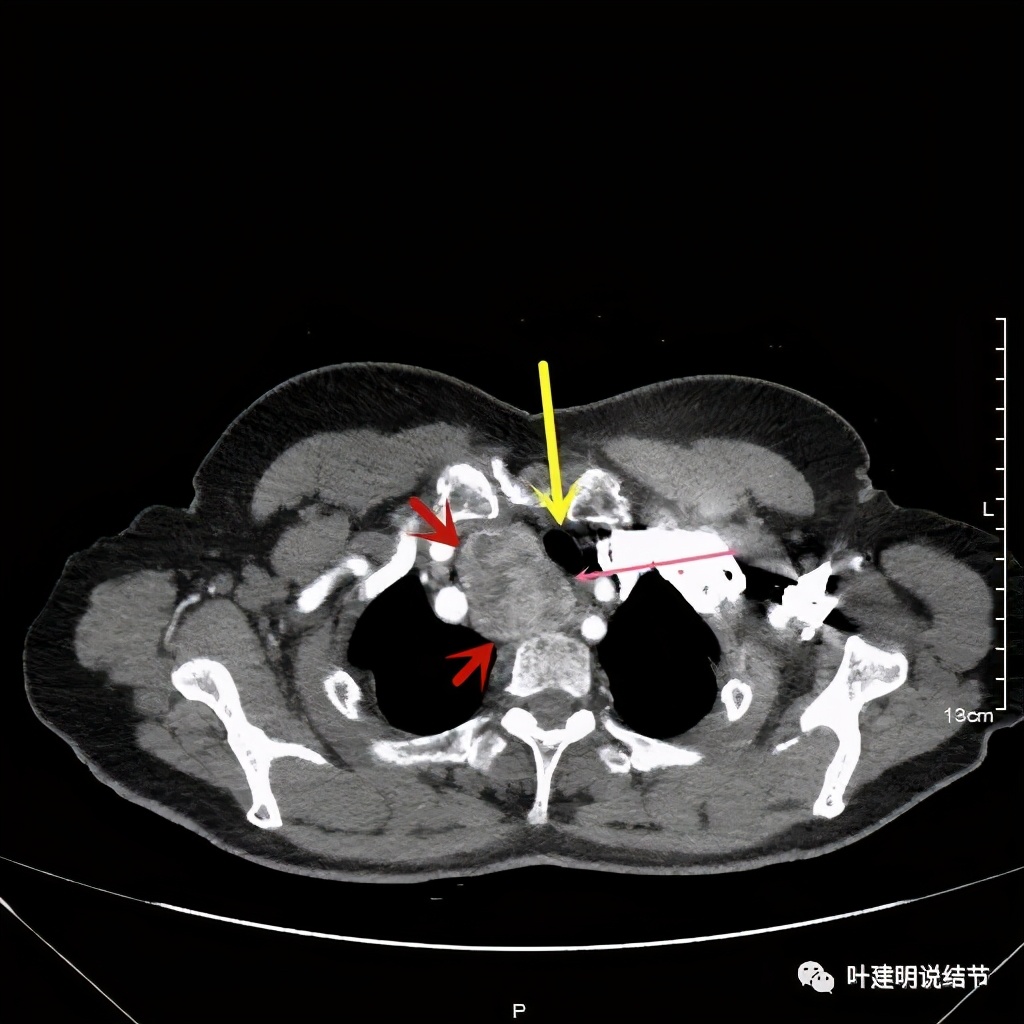

上图红色示肿瘤,粉色示肿瘤与气管关系密切,而且肿瘤密度不均杂乱

上图红色示肿瘤,黄色示气管,粉色示肿瘤与气管关系密切,而且肿瘤密度不均杂乱

上图红色示肿瘤,黄色示气管,粉色示肿瘤与气管关系密切,桔色示左无名静脉,蓝色示上腔静脉,而且肿瘤密度不均杂乱